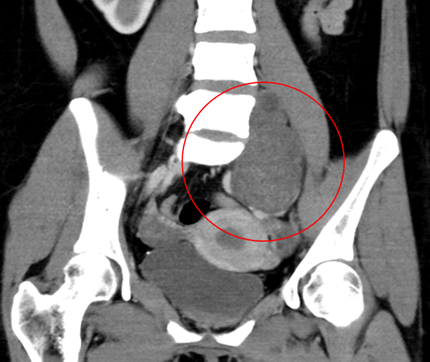

患者为54岁女性,自幼发现全身多发皮肤、皮下结节,并持续增多、变大,其中左臀部肿物尤为明显,因短时间内生长迅速、影响正常行走和排便功能来诊。患者体表可见大量散在皮肤结节、牛奶咖啡斑,MRI提示肿物信号混杂,膀胱、子宫、直肠明显受压右移,CT示该肿物跨盆腔内外,较大层面范围约13.5×8.7×13cm,密度欠均,夹杂囊变,累及左侧闭孔内肌、梨状肌、肛提肌及左侧外阴。

图片 12.png

图片 13.png图片 11.png